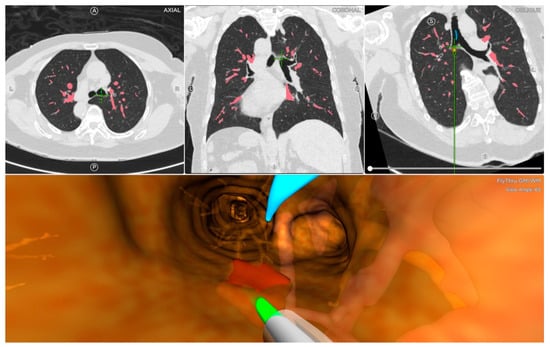

All chest CT examinations for all patients were configured with 1 mm intervals in the Digital Imaging and Communications in Medicine format. The location board was placed on the patient’s back to create a localizing marker for the Archimedes VBN with possible transparenchymatous access. The CT images were uploaded into the Archimedes system to construct a 3D virtual airway leading to the pulmonary lesions. Archimedes can display different paths, determine the best path to avoid blood vessels, and measure the distance from the region of interest to the pleura [13]. After identifying the target lesion, the software can calculate and create the planning route (Figure 3). General anesthesia was inducted to all patients in the supine position. After, navigation with bronchoscopy (mentioned in the ENB procedure) was performed using the tools along the selected pathway to the target lesion of interest to utilize biopsy forceps and/or an 18-gauge needle to puncture the airway wall that was felt best suited to obtain a tissue sample. One chest surgeon performed the VNB procedures (Y. M. T. had more than five years of experience with bronchoscopic procedures and a mean of 100 procedures·yr−1). In the Archimedes Access Kit, there was an 18 ga FleXNeedle, sheath, and dilation balloon that could be utilized for the BTPNA, which was performed for 7 cases in our retrospective review. The BTPNA was performed with a robot-supported C-arm cone-beam CT, which featured 3D imaging using Syngo DynaCT Large Volume (Artis Pheno; Siemens Healthcare GmbH, Forchheim, Germany) to provide a real-time image model to mark the pulmonary lesions. This entailed locating the point of entry (POE) in the bronchus wall with/without balloon dilation, where a radiopaque sheath or biopsy forceps was introduced through the lung parenchyma to access the target lesion [15]. On average, approximately 3–4 samples were obtained using forceps in the Archimedes VNB procedure. The evaluation of the pathological biopsy specimens was then performed in both the ENB and VNB procedures. During and after surgery, data on the complications and management were documented. All patients received a postprocedural chest film within 2 h postoperatively to evaluate the possible postoperative complications. The postoperative period was uneventful.

Figure 3. Archimedes virtual navigational bronchoscopy leading to the lesion.